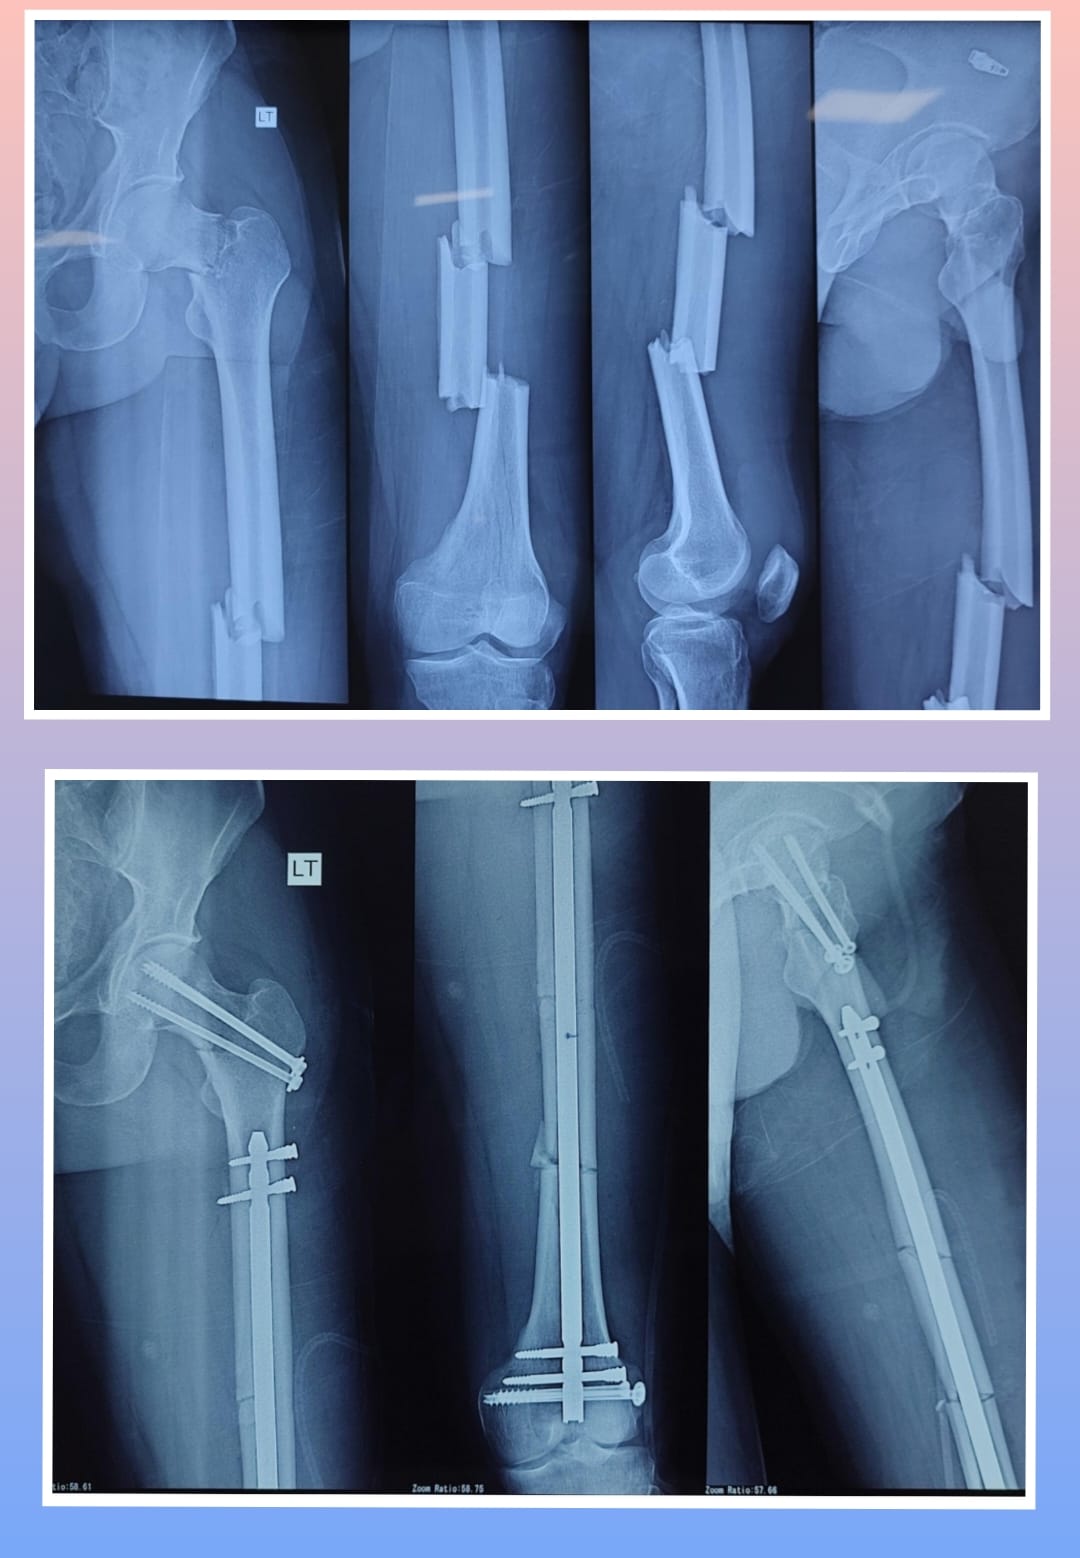

X-ray

Surgeries